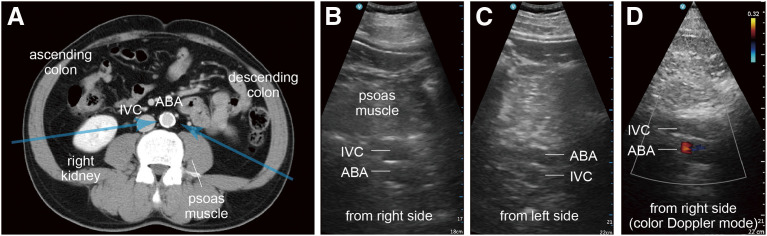

Objectives: With improved surgical outcomes for non-ruptured abdominal aortic aneurysm (AAA), the primary objective has shifted toward the detection of asymptomatic AAA. Since ultrasonographic visualization from the anterior abdominal wall is often obstructed by intestinal gas, utilizing additional bilateral posterior approaches via the retroperitoneal tissue may be beneficial. This study investigates the feasibility of assessment using three approaches through computed tomography (CT) data analyses. Methods: The study included 27 surgical patients with AAA (AAA group) and 37 patients with other atherosclerotic diseases (non-AAA group). CT data were analyzed to locate the infrarenal aorta relative to the navel, availability of acoustic window, depth of the aorta, and assessment of aneurysmal aorta using three approaches. Results: The "AAA area" for ultrasonographic screening may be set at 0-4 cm above the navel. An acoustic window was unavailable in 8.1% of AAA cases and 7.4% of non-AAA cases in the anterior approach; however, it was available in the posterior approach. Although the depth of the aorta was greater in obese patients, it remained within 20 cm. Conclusion: Ultrasonographic screening is feasible by incorporating posterior approaches in cases where anterior visualization is difficult, enhancing the detection of asymptomatic AAA.